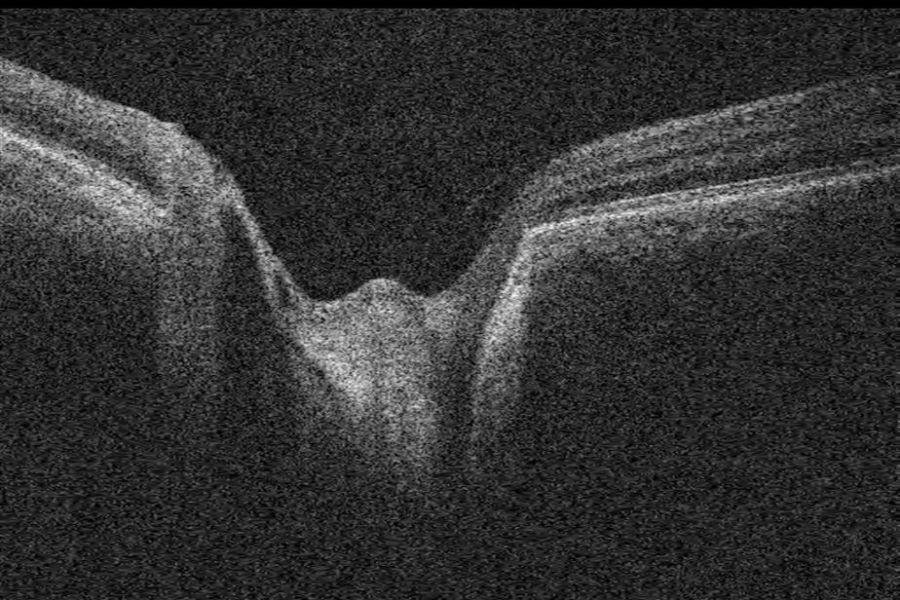

Grubenpapille (siehe Anmerkung)

Papillengrube (аббревиатура: Grube)